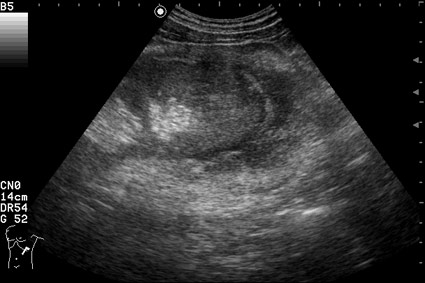

Изменения левой почки у мужчины 56 лет

Жалобы на дискомфорт в пояснице слева. Травма поясницы в анамнезе. Анализы крови и мочи нормальные.

Как трактовать выявленные изменения? Какова тактика врача УЗД в данной ситуации?

На сонограмме представлена

лимфома почки

. Диагноз доказан морфологически.